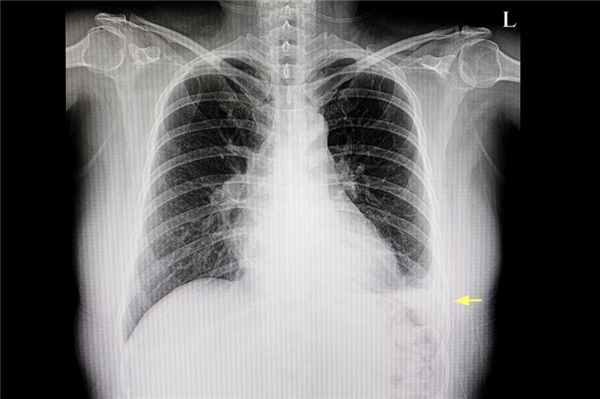

Рентгенологическое изображение легкого пациента, где виден плевральный выпот (желтая стрелка)

Первичный осмотр проводит врач-терапевт , врач общей практики или пульмонолог . Дальнейшее ведение больных осуществляется профильным специалистом: кардиологом , гепатологом, нефрологом, эндокринологом . В стационаре пациента наблюдает торакальный хирург.

Правосторонний гидроторакс (рентгенография органов грудной клетки